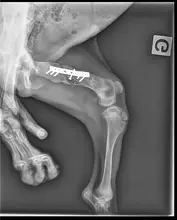

Après avoir subi une lourde intervention chirurgicale pour lui placer une plaque en métal, Milagro s'est retrouvé en famille d'accueil et cette association nous a contactés pour récupérer le chien, la famille d’accueil ne pouvant plus le garder.